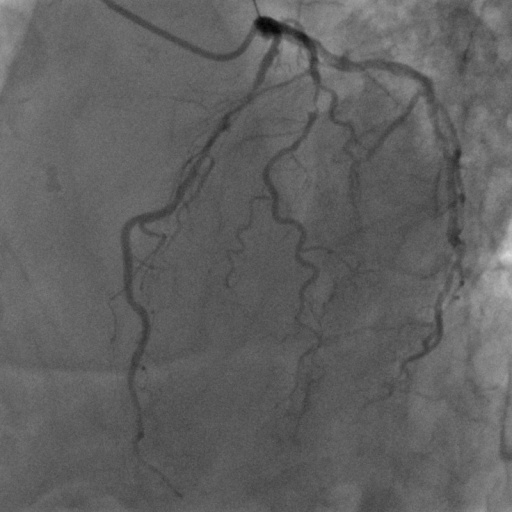

| Image | Ground truth | Video frame | Ground truth | Video frame | Ground truth |

| XCAD [33] | CADICA [19] | Our XACV dataset | |||

4.1 XACV Dataset

We collect 111 complete records of coronary artery X-ray videos, encompassing the injection, flow through the blood vessels around the heart, and dissipation of the contrast agent. Subsequently, we establish the XACV (X-ray Angiography Coronary Video) dataset. Each video consists of varying numbers of high-resolution coronary artery X-ray images. We invite experienced radiologists to annotate the vascular regions, focusing on one or two frames where the contrast agent is most prominent in each video. The XCAD dataset contains only a single image, and the CADICA video dataset does not provide corresponding ground truth. Therefore, in the following experiments, we conduct all the analyses on our collected XACV dataset and the corresponding GT for each sequence. In Figure 5, we show that compared to other publicly available datasets, XCAD [33] and CADICA [19], our dataset exhibits finer annotations in the vascular regions, providing an advantage for future related tasks. The development and use of our dataset have been approved by our institution’s IRB.